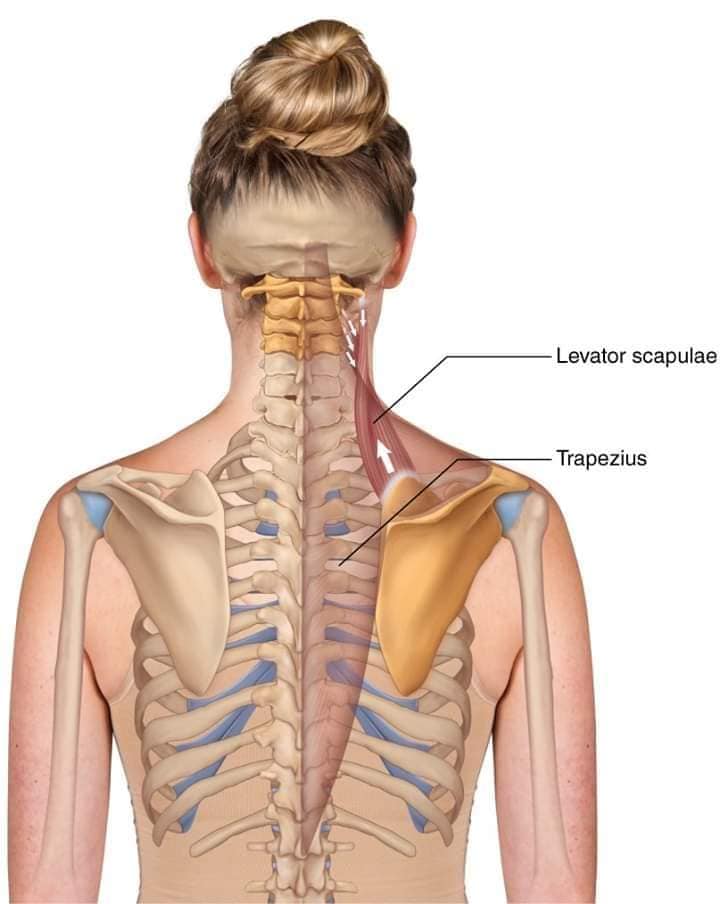

М'язи задньої групи

М'язи, що розширюють шию: М'язи, що розширюють шию: включають трапецієподібний м'яз, який бере участь у піднятті плечей і розширенні шиї.

Поверхневі спинні м'язи

М'язи, що піднімають лопатку: Трапецієподібний м'яз: великий м'яз, що покриває верхню частину спини. Його функція - підтримка і рух лопаток, а також забезпечення стабільності хребта.